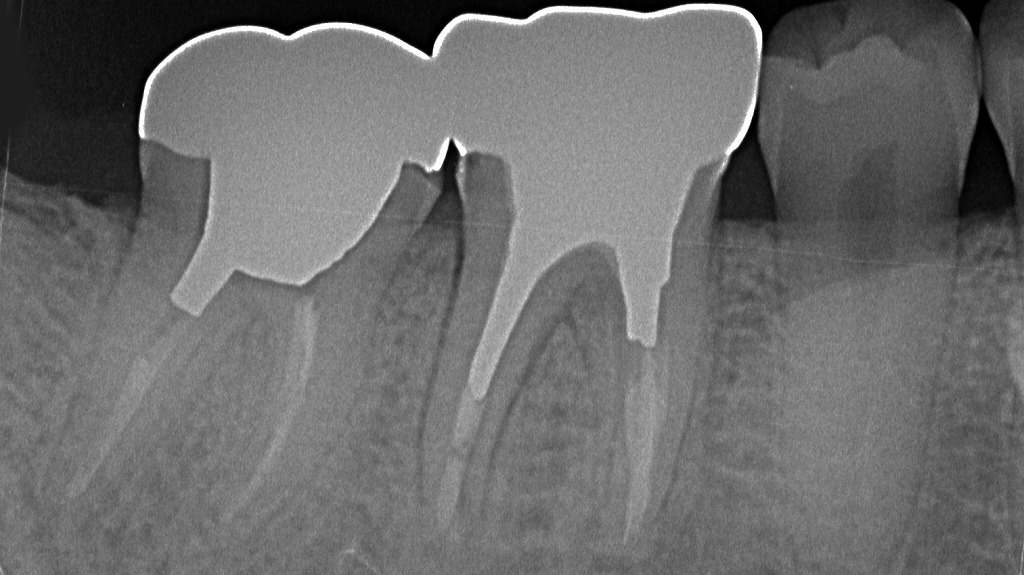

このデンタルX線画像は、上顎右側第一大臼歯(6番)を中心に撮影されたものです。赤い矢印が示す部位に注目すると、以下のような所見が見られます。

🔍 所見の詳細

- 部位:上顎右側第1大臼歯(6番)

- 問題箇所:遠心側コンタクト部(7番との間)に明瞭な透過像(黒い影)を認めます。

- 所見内容:

この透過像は**象牙質にまで進行したう蝕(C3レベル)**を示唆しています。う蝕が歯髄腔に近接しており、髄室の輪郭もやや不明瞭になっています。

歯髄炎が発症している可能性が高く、自発痛や咬合時痛、頭痛を伴うケースです。

🦷 診断

- 診断名:上顎右側第一大臼歯 遠心う蝕(C3)

- 臨床症状の推定:

- 自発痛(特に夜間痛)

- 温冷水刺激による強い疼痛

- 咬合時の違和感または疼痛

- 頭痛や放散痛(上顎洞周囲に広がることもあり)

💡 治療方針の考え方

- **歯髄診査(電気・温冷刺激)**により可逆性・不可逆性歯髄炎の鑑別。

- 不可逆性歯髄炎の疑いが強い場合は、**根管治療(抜髄)**が必要。

- う蝕除去後の支台歯形成を行い、クラウン修復。

- 隣接歯とのコンタクト部清掃性を改善し、再発防止策(フロス指導など)も重要。

下顎6番・7番は深いむし歯のため抜髄処置を行い、根管内を清掃・消毒したのち適切に根管充填を実施しました。その後、歯質の強度を確保するためメタルコアを築造し、最終補綴としてクラウンを装着しています。根尖部に異常所見はなく、補綴物の適合も良好に維持されています。